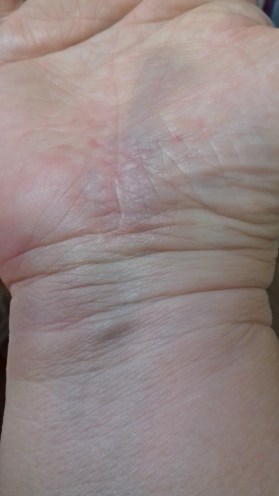

Cette fois c’est la main et le poignet qui ont morflé !

J’ai eu beau dire que c’est la main qui me faisait le plus souffrir, ils se sont concentré sur le poignet. Je n’ai pas pu voir les radios bien sur et cette main me fait parfois encore mal.